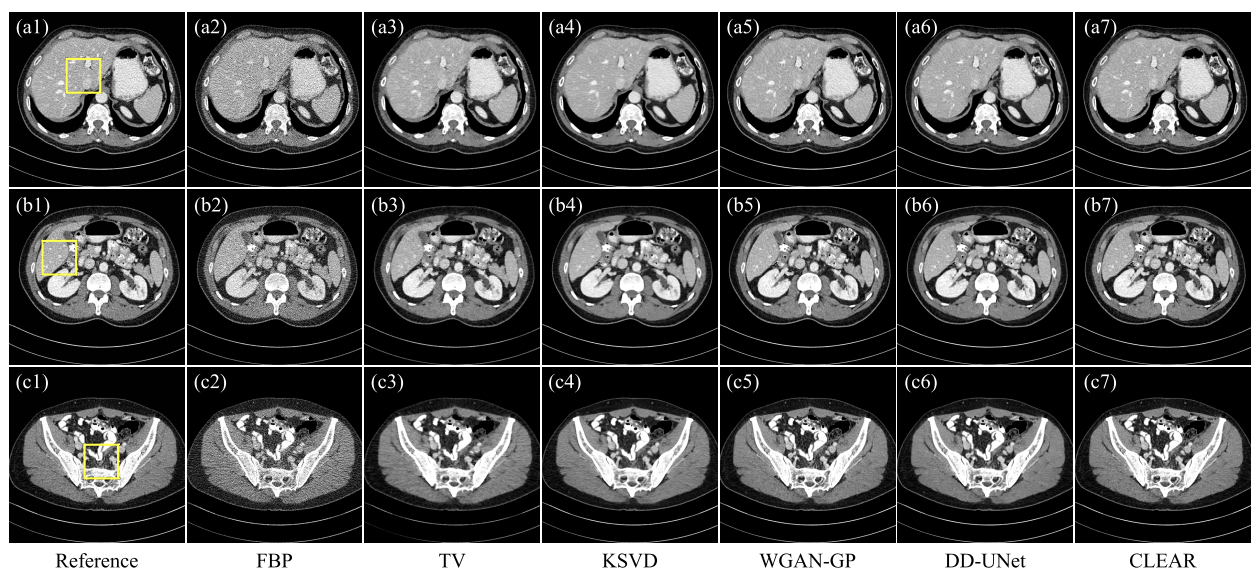

- 비교 모델: FBP, TV(반복 재구성 방법), KSVD(딕셔너리 학습 알고리즘), WGAN-GP(생성 모델을 기반으로 한 후처리 기법), DD-UNet(연속된 네트워크 처리 알고리즘)

- 실제 데이터

- FBP: 노이즈는 이미지의 미세한 특징을 심각하게 손상

- TV: 블록 artifact 발생( c3)

- KSVD: 흐림효과, 미세한 구조 손실(d4)

- DD-UNet:노이즈 억제 x, 세부사항 보존 x

- WGAN-GP , CLEAR: 좋은 시각적 인식(CLEAR가 구조적 충실도에서 더 유망한 성능)

- CLEAR: 가장 높은 SSIM과 PSNR,가장 낮은 MAE

- TV>WGAN-GP, DD-UNet: 데이터 기반 방법-> 실제 프로젝션과 시뮬레이션된 프로젝션 간의 불일치